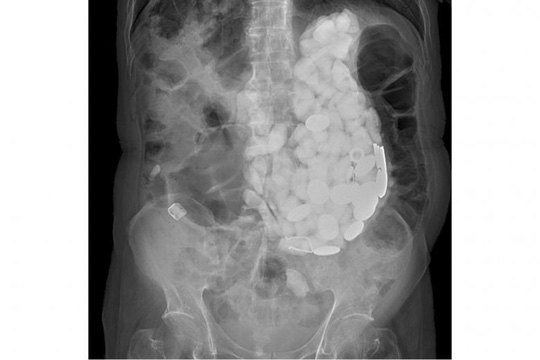

Old  Default Ca phẫu thuật hy hữu ở Hàn Quốc, lấy ra 2kg sỏi, nắp chai và tiền xu từ bụng bệnh nhân

Một bệnh nhân bị chứng rối loạn lo âu được cấp cứu tới bệnh viện với triệu chứng đau thượng vị dữ dội. Sau khi thực hiện xét nghiệm, các bác sĩ Hàn Quốc đã thực hiện ca phẫu thuật hy hữu để lấy sỏi, nắp chai và tiền xu ra khỏi bụng của một bệnh nhân này.

Ca phẫu thuật này được đăng tải trên Asian News Network (ANN) ngày 23-2. Bác sĩ Pyong Wha Choi của Bệnh viện Ilsan Paik thuộc Trường ĐH Y Inje ở TP Goyang – Hàn Quốc, cho biết bệnh nhân là một người đàn ông 54 tuổi, nhập viện khẩn vì đau thượng vị, có dấy hiệu viêm loét dạ dày.

Theo ANN, ngoài chứng thiểu năng trí tuệ bẩm sinh, bệnh nhân này còn bị chứng rối loạn lo âu trong suốt 10 năm qua. Trong suốt quá trình kiểm tra y tế, các bác sĩ cho biết họ phát hiện "thứ gì đó giống như sỏi" bên trong bụng của bệnh nhân. Kết quả chụp X-quang cho thấy có nhiều vật thể lạ trong bụng của người này.

Ảnh chụp X-quang cho thấy dạ dày của bệnh nhân chứa đầy vật thể lạ. Ảnh: PUBS.SCIEPUB.COM

Trước đây, bệnh nhân này từng nhập viện và ông ta có thói quen nuốt sỏi, nắp chai và tiền xu mỗi khi lo âu, mặc dù đã được các bác sĩ khám và kê thuốc.

Để lấy sỏi, nắp chai và tiền xu ra khỏi bụng bệnh nhân, các bác sĩ tiến hành nội soi. Tuy nhiên, vì số lượng vật thể quá nhiều nên sau đó họ buộc phải phẫu thuật. Tổng khối lượng sỏi, nắp chai và tiền xu trong bụng của người này là 2 kg.